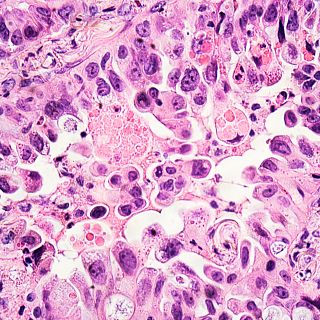

Hace unos días, el presidente de Estados Unidos, Joe Biden, anunciaba la intención de reducir a la mitad las muertes por cáncer en 25 años. Hoy en Por tres razones, analizamos cómo avanza la investigación en este aspecto. El oncólogo barcelonés Antoni Ribas, de la Universidad de California en Los Ángeles (UCLA), reconocido como uno de los líderes mundiales en in-munoterapias anti-tumorales, nos explica las diferentes líneas de investigación que se desarrollan en la actualidad y que, si continuan, permitirán tratar la mayoría de tipos de cáncer en unos años. Daniel Herranz, doctor en Farmacia que lleva una década estudiando cómo influye la genética y el metabolismo en el cáncer, nos cuenta las diferencias que hay entre países como España o Estados Unidos, con importantes saltos en términos de sistemas públicos e inversión en investigación.